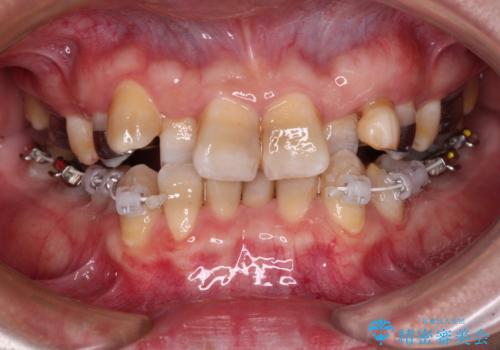

- 上下の前歯のデコボコを改善したいと来院された患者様です。

上顎の歯列幅が狭く、それによって歯が並ぶスペースが不足しています。

また下顎の歯列幅も制限され、内側に歯が倒れています。

それらを改善するため上顎に拡大装置を用いて、審美装置にてワイヤー矯正を行いました。